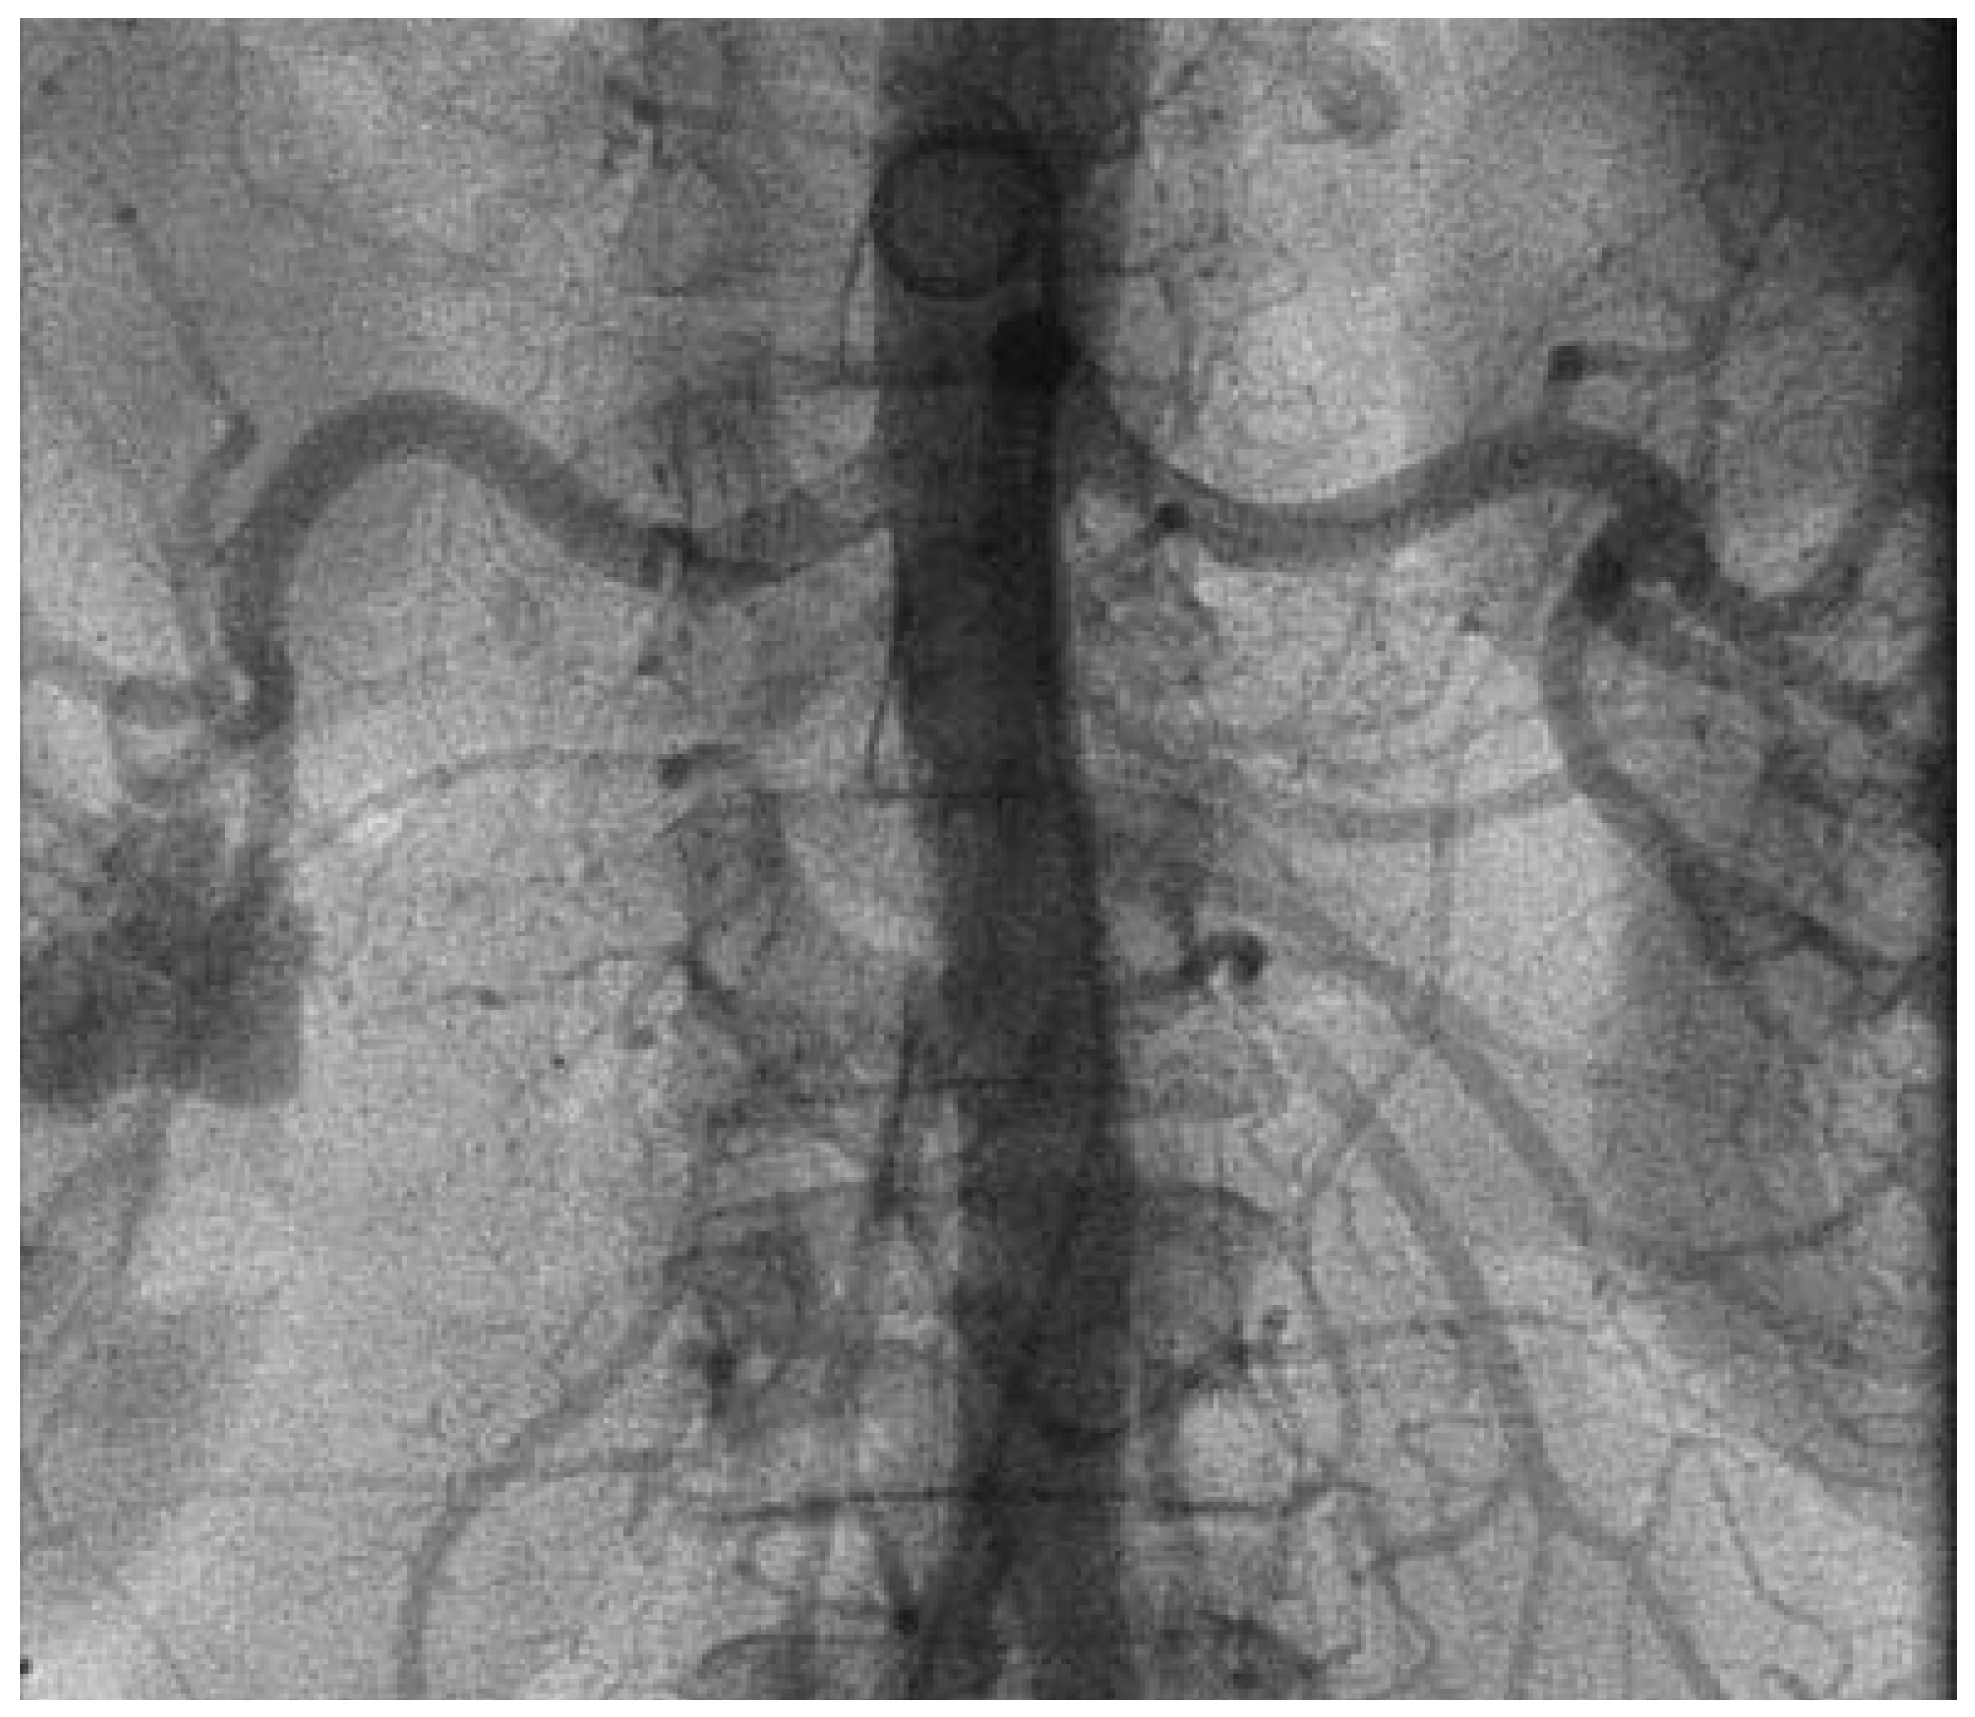

Abbildung 3.

Initiale Darstellung der rechten und linken Nierenarterie zur Überprüfung der Anatomie vor Durchführung der renalen Sympathikusdenervation.

Die Durchführung der renalen Sympathikusdenervation erfolgte im standardmässig eingerichteten Herzkatheterlabor unter monoplaner Durchleuchtung. Die Vorbereitung der Patientin entsprach im Wesentlichen der einer Koronarangiographie. Nach lokaler Anästhesie der vorgesehenen Punktionsstelle erfolgte die Punktion der linken Arteria femoralis. Mittels Seldinger-Technik wurde eine 8-French-Schleuse in das Gefäss eingeführt. Anschliessend erfolgte nochmals die Darstellung der renalen Gefässanatomie (Abb. 3). Es zeigte sich entsprechend dem magnetresonanztomographischen Vorbefund eine geeignete Anatomie beider Nierenarterien. Nun wurde ein 8-French-LIMA-Führungskatheter eingebracht und die linke Nierenarterie intubiert. Über einen Führungsdraht (BMW, Abbott Laboratories, Illinois, USA) wurde in der Folge ein 5-F-Multipurpose-Katheter bis zur Bifurkation der Nierenarterie eingeführt. Nach Rückzug des Führungsdrahtes wurde über den liegenden 5-F-Katheter der Symplicity™-Ablationskatheter in der linken Nierenarterie platziert. Danach wurde der 5-F-Katheter zurückgezogen und ein Kontakt der Spitze des Ablationskatheters mit der Nierenarterienwand hergestellt (Abb. 4).